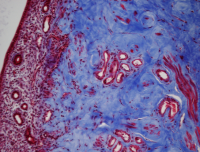

Microscope image of tissue stained in blue and red.

The team discovered that ANTXR2 regulates enzymes called matrix metalloproteinases (MMPs), which promote remodeling of the extracellular tissue—called extracellular matrix (ECM) —of the cervix.  During pregnancy, the ECM helps to maintain cervical firmness and structure. At the end of the pregnancy, ANTXR2 promotes ECM remodeling so that the cervix softens and dilates, a process called ripening. “The mice that did get pregnant,” said Dr. Kitajewski, “were unable to deliver because their cervices failed to ripen and their uterine tissue had excessive ECM.”